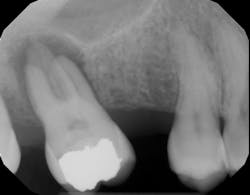

The radiolucency you see in figure 2 is a hole in the bone where inflammation is occurring, but the radiolucency is not the infection. This important concept is often missed: that the radiolucency itself is not the infection; the infection is in the root canal system within the tooth. The radiolucency is just one sign that the root canal is harboring infection. Healing of a periapical radiolucency occurs when the infection level inside the root canal is reduced below a certain threshold and the body has deemed the contents of the root canal as no longer posing a threat. The threshold of what the body feels is a safe level of bacteria is different for each person.

The goal of getting the tooth treated with a root canal or root canal retreatment is reduction of the bacteria and removal of the food source that helps bacteria thrive (pulp tissue and inflammatory proteins). The bone will fill back into the hole or osseous defect once the tooth canals are treated and the infection is removed (figure 3). Depending upon the size of the bone lesion, healing may take anywhere from three to 12 months.